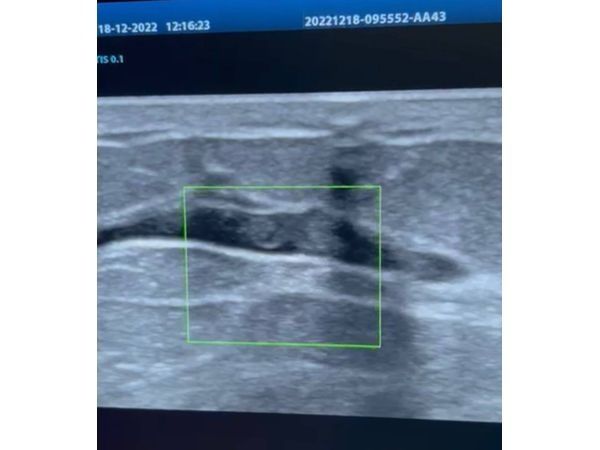

При ультразвуковом исследовании (УЗИ) отмечалась локальная дуктэктазия (расширение протоков), единичные кисты в обеих молочных железах. По УЗИ также поставили категорию BI-RADS 2 для обеих молочных желёз.

Не выдавливая контрастное вещество, пациентке вновь сделали УЗИ. И при наполненном контрастом протоке уже можно было обнаружить внутрипротоковое образование.